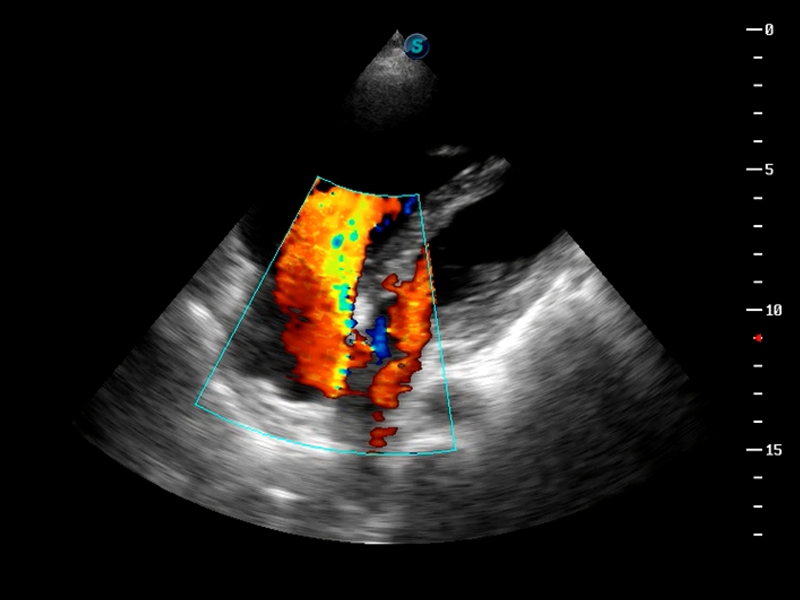

S9便携式彩色多普勒超声诊断仪是1xBET研发的高端便携彩超设备,外观设计新颖、产品性能卓越。S9在便携超声领域采用了突破传统的触摸屏交互设计,并以先进的软件硬件技术和设计理念,为您带来清晰的图像质量、稳定的工作性能和便捷的操作体验。

TDI组织多普勒成像

AutoC智能血流追踪